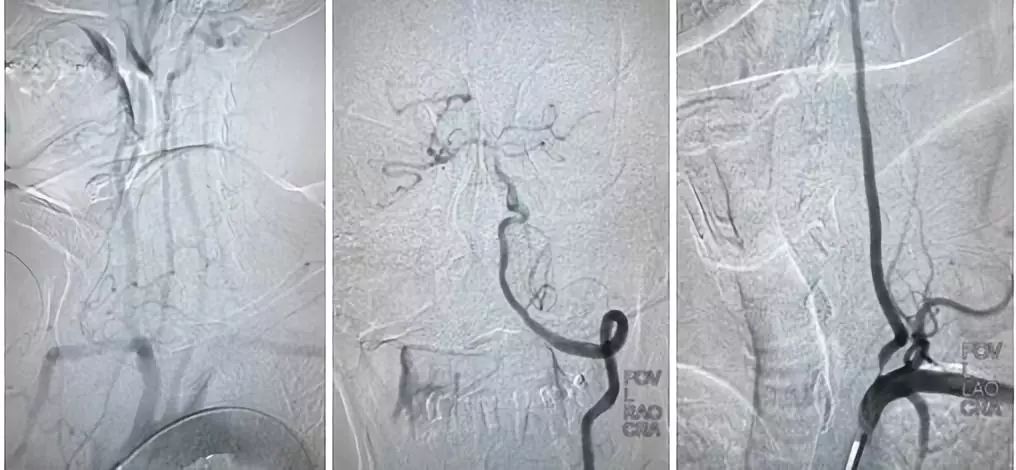

DSA结果提示:左侧颈内动脉次全闭塞,远端未见显影,左侧大脑中动脉闭塞,前交通动脉开放,左侧椎动脉起始部重度狭窄(图3-5)。

图3

图4

图5